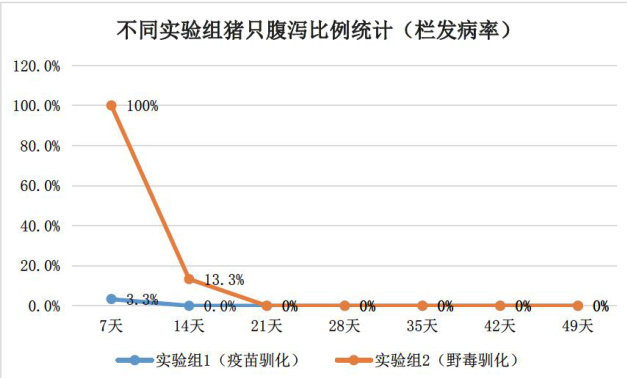

实践案例 | 不同PED驯化后备猪方式的效果评价研究

实践案例 | 不同PED驯化后备猪方式的效果评价研究